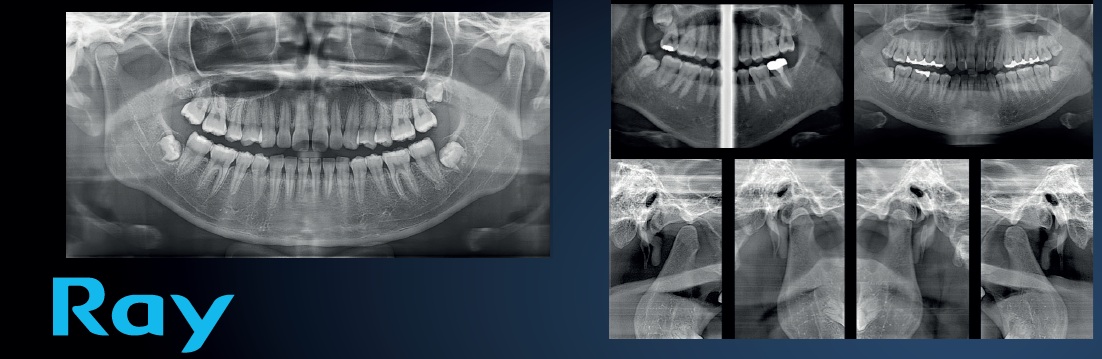

Découvrez la puissance de l'imagerie 3D avancée avec le RAYSCAN Alpha Plus 160. Cette solution tout-en-un combine scanners CBCT, radiographies panoramiques et céphalométrie dans un appareil compact et facile à utiliser. Grâce à une qualité d'image exceptionnelle allant jusqu'à 70 µm, un champ de vision variable jusqu'à 16 × 10 cm et une dose de rayonnement réduite, le RAYSCAN vous accompagne à chaque étape de votre flux de travail clinique – du diagnostic à la planification du traitement.

Qu'il s'agisse d'implantologie, d'orthodontie, d'endodontie ou de chirurgie maxillo-faciale, le RAYSCAN Alpha Plus 160 fournit rapidement et de manière fiable les informations dont vous avez besoin. Avec son interface intuitive, son temps de scan rapide et ses outils logiciels avancés, cet appareil élève votre cabinet à un niveau supérieur de précision, d'efficacité et de soins aux patients.

Panoramique avec autofocus automatique

Grâce à la technologie Adaptive Moving Focus, les meilleures couches d'image sont automatiquement sélectionnées pour des radiographies panoramiques claires et précises. Cela facilite l'évaluation de l'état parodontal de vos patients et la localisation exacte des lésions.